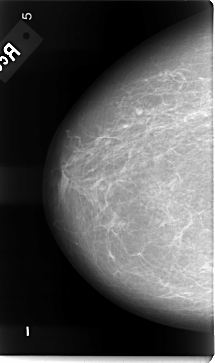

B_3086_1.RIGHT_MLO

LEFT_MLO LINES 4616 PIXELS_PER_LINE 2832 BITS_PER_PIXEL 12 RESOLUTION 50 OVERLAY

FILE: B_3086_1.LEFT_MLO.OVERLAY

TOTAL_ABNORMALITIES 1

ABNORMALITY 1

LESION_TYPE MASS SHAPE OVAL MARGINS OBSCURED-ILL_DEFINED

ASSESSMENT 3

SUBTLETY 2

PATHOLOGY MALIGNANT

TOTAL_OUTLINES 1

BOUNDARY